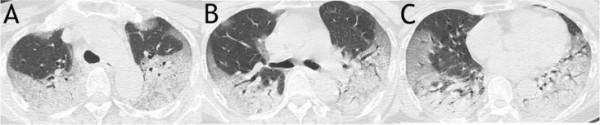

Fig 1. A sample scoring on CT images of a 63-year-old woman from mortality group demonstrated a total score of 63. It was calculated as: for upper zone (A), 3 (consolidation) × 3 (50–75% distribution) × 2 (both right and left lungs) + 2 (ground glass opacity) ×1 (< 25% distribution) × 2 (both right and left lungs); for middle zone (B), 3 (consolidation) × 2 (25–50% distribution) × 2 (both right and left lungs) + 2 (ground glass opacity) × 2 (25–50% distribution) × 2 (both right and left lungs); for lower zone (C), 3 (consolidation) × (2 (25–50% distribution of the right lung) + 3 (50–75% distribution of the left lung)) + 2 (ground glass opacity) × (2 (25–50% distribution of the right lung) + 1 (< 25% distribution of the left lung)) Yuan et al, 2020 (CC BY 4.0)

In this patient group, the authors associated clinical features identified from computed tomography (CT) scans of patients’ lungs with eventual outcomes. They scored patients based on features they observed such as ground glass opacity, abnormality on both sides, and widespread distribution of pathology in the lungs, to produce an overall severity score for each patient.

Of the 27 patients, who were mostly older adults (median age 60), 17 (63 percent) recovered and were discharged from hospital, while 10 (37 percent) died of the virus. Patients with underlying health conditions including hypertension, diabetes and cardiac disease were more likely to die of the virus than patients without such comorbidities, and older patients were also more likely to die, though there was no difference between genders. Patients with a higher (more severe) score at CT scan were much more likely to die of COVID-19 – the average score of patients who died was 30, compared to 12 in patients who recovered.